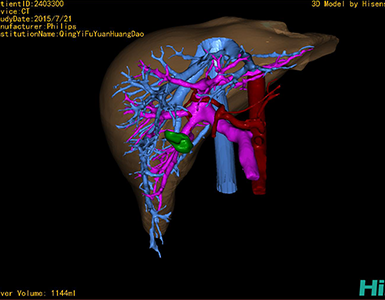

将0.625mm双源薄层CT资料的静脉期和动脉期Dicom格式文件导入海信CAS系统。

通过调节窗宽窗位调整CT序号,对肿瘤,肝实质,胆囊,下腔静脉,肿瘤,肝动脉、门静脉及肝静脉等进行三维重建;系统自动计算肿瘤体积和肝脏体积。

模拟手术操作,自动计算切除肿瘤体积。肝脏体积为1096ml,胰腺肿瘤体积为115.5ml,通过比对12-13岁正常肝脏体积为1116.86±158.78 ml,通过术前模拟手术,精准判断切除后肝脏体积无明显变化,避免肝衰竭发生。

术前三维重建:

重建图片